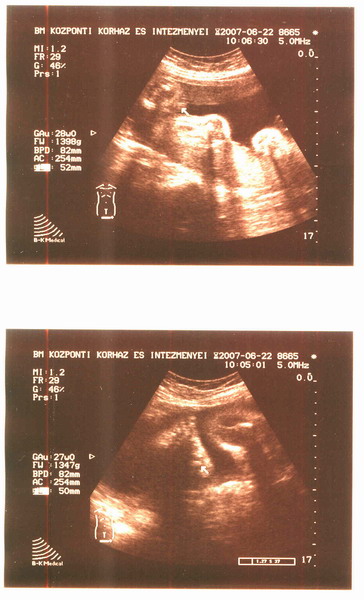

Köszönöm aranyosak vagytok, jól estek a dicséretek, mert hát néha nem úgy látom magam, szóval tudjátok. Hát voltunk 4 D szombaton, a kissrác bealudt:)

Majd teszek fel képeket:) meg a babaszobáról is, meg a gardróbról is, csak mindig elfelejtem.